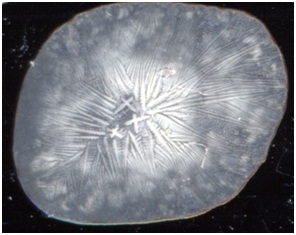

Среди

тезиографических картин лизата лейкоцитов больных гломерулонефритом можно было

выделить 2 основных морфотипа. Первый морфотип встречался у 7 больных

гломерулонефритом (то есть в 19 % случаев). Второй морфотип встречался у 29

больных гломерулонефритом.

Первый

морфотип лизата лейкоцитов больных гломерулонефритом представлен на рисунке 1.

Рис. 1 первый морфотип

тезиограмм плазмы крови больных гломерулонефритом.

Этот

морфотип лизата лейкоцитов больных гломерулонефритом характеризовался наличием больших кристаллов виде крестов в

центре тезиограммы, от кристаллов отходили в виде лучей до самых краев

тезиограммы лизата лейкоцитов длинные кристаллы-тяжи.

Второй

морфотип лизата лейкоцитов больных гломерулонефритом представлен на рисунке 2.

Рис. 3 второй морфотип

лизата лейкоцитов больных гломерулонефритом

морфотип лизата лейкоцитов больных гломерулонефритом характеризовался наличием

равномерно распределенных по всей фации небольших кристаллов в виде крестов,

имелись кристаллы в виде прямоугольников (рисунок 3). Иногда на периферической

части фации могли встречаться кристаллы-тяжи.